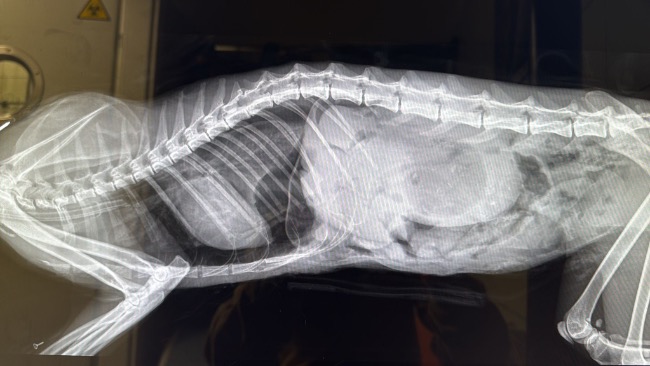

Obraz po:

Wczoraj przeszła pilną operację przepukliny przeponowej. Jej narządy przemieściły się i zaplątały w jelita, powodując bezpośrednie zagrożenie życia. Obraz, który zobaczyliśmy po otwarciu jamy brzusznej, wzbudził ogromny niepokój zespołu operacyjnego.

Część narządów wymaga dalszej, wnikliwej diagnostyki. To nie koniec jej Walki. To dopiero początek.